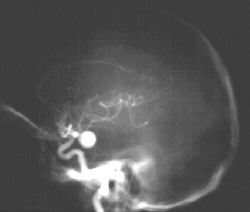

Refer to this picture for question 1.

1. The following signs may occur in this patient: